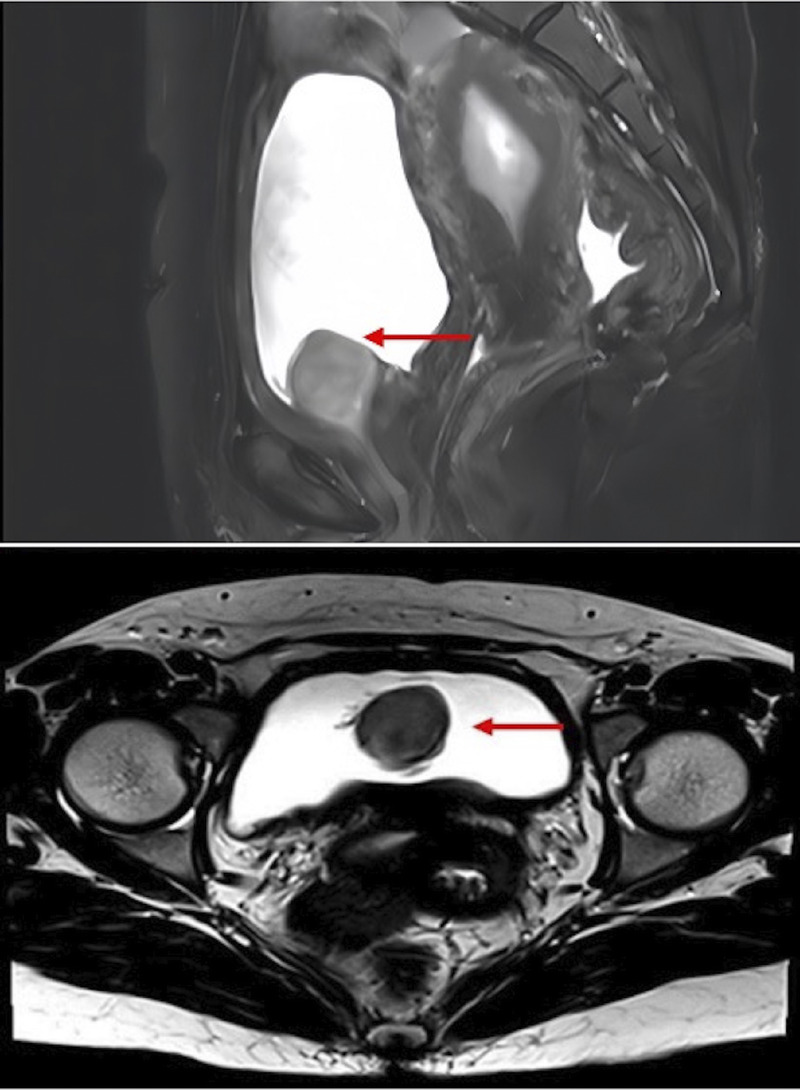

This article reported the diagnosis and treatment of cystitis glandularis (CG) co-occurring with bladder neck leiomyomas. We retrospectively analyzed the clinical data of a single case of CG with bladder neck leiomyoma. A 31-year-old Chinese woman was given a diagnosis of CG and bladder neck leiomyoma. The mass and surrounding bladder mucosal lesions were entirely excised via transurethral resection, leaving a clean margin of healthy tissue. Histopathological analyses confirmed the diagnosis of CG and bladder neck leiomyoma. The patient remained asymptomatic throughout the follow-up period, with no indication of recurrence. Cystitis glandularis co-occurring with bladder neck leiomyoma requires careful examination, and surgery remains the best treatment option for these diseases.